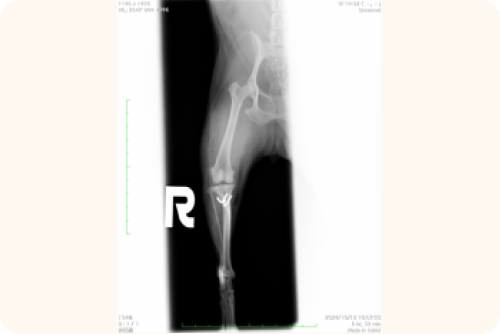

レントゲン検査

X線撮影により、以下の点を詳細に確認します。

• 膝蓋骨の位置と脱臼の方向

• 骨の変形や捻れ

• 変形性関節症の進行度

• 関節炎の有無

この検査結果は、手術の必要性や具体的な手術方法を決定する上で重要な情報となります。

骨の位置関係や、前十字靭帯損傷時に見られる特徴的な所見(ファットパットサインなど)を確認します。

視診や触診後、レントゲン検査を行い、骨がどのような位置にあるのかを詳しく調べます。また、レントゲン写真では膝の関節内にある脂肪組織の位置も確認します。この脂肪組織の位置が変わっていることで、前十字靱帯が傷んでいないかどうかの手がかりを得ることができます。